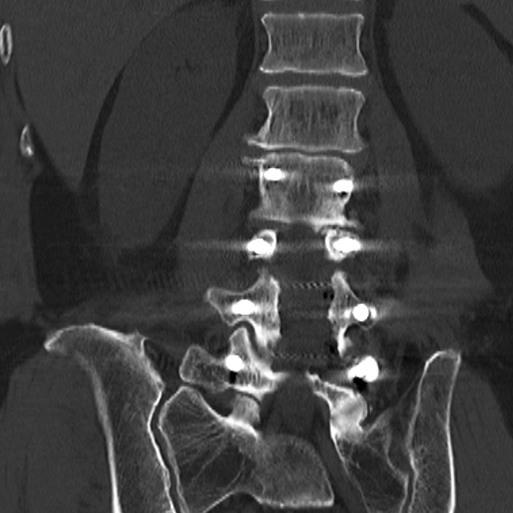

术后复查X线、CT

椎弓根螺钉内固定技术是目前脊柱手术中最常应用的固定技术,但在椎弓根置钉过程中存在损伤神经与血管的风险。提高置钉安全性及成功率一直是脊柱外科医师研究的重要内容。

既往脊柱外科医生仅能根据术前影像学资料制定手术方案,但3D打印技术的出现,可以客观、立体、快速地复制出患者目标脊柱的1:1实物模型,并可根据需要建立不同的剖面打印图,利于术者更直观地观察特定区域的骨、血管、脊髓神经等毗邻关系和个体化解剖特点,制定精细化、个体化的手术方案,从而在一定程度上提高了椎弓根螺钉置入或某些穿刺诊疗操作的精准性和安全性。